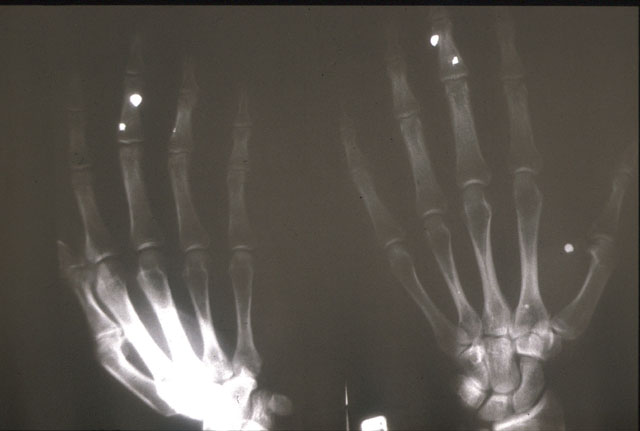

perdigo.jpg (31264 bytes)

Perdigones alojados en las manos